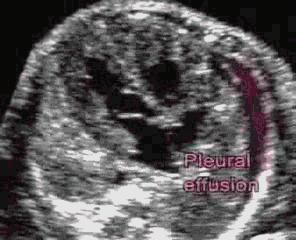

c.心脏